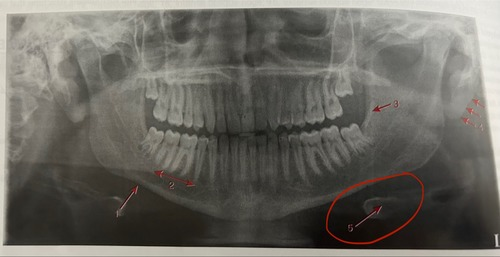

Nutrient canals

Mental foramen

External oblique ridge

Inferior border of mandible

Submandibular fossa

Hyoid bone